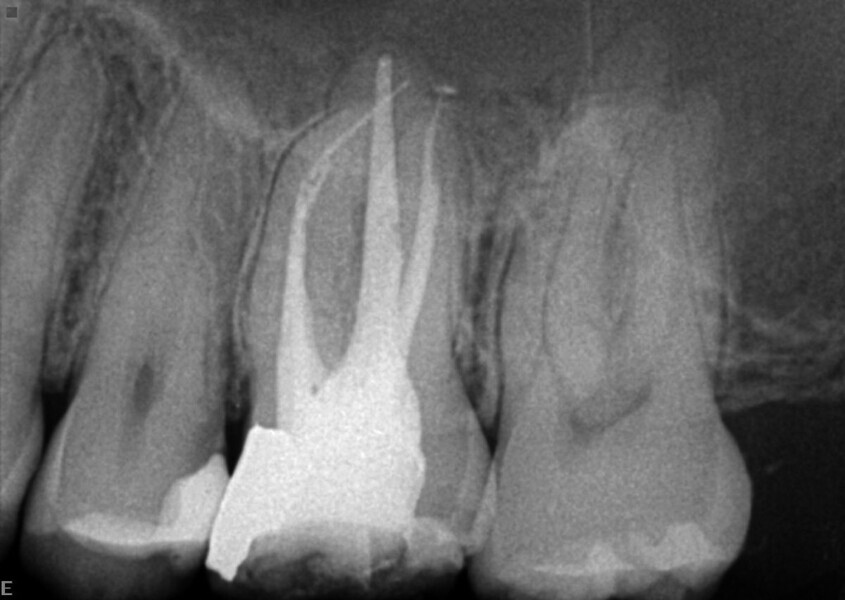

Maxillary sinus and root canal therapy complications